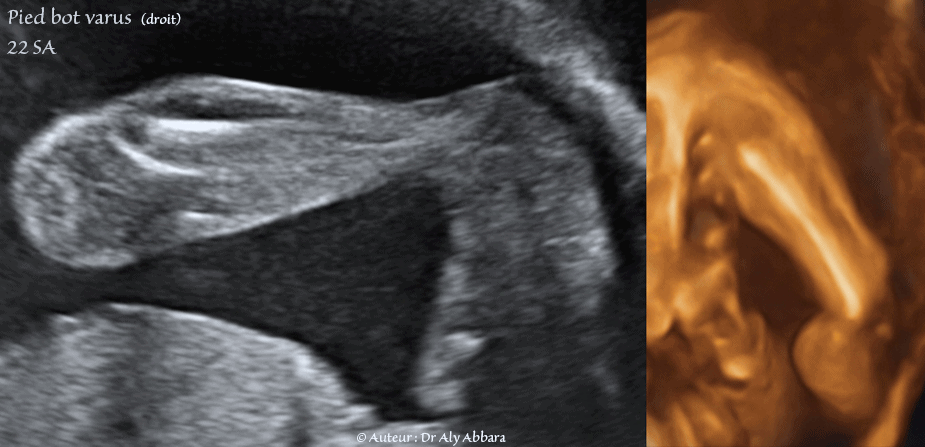

Pied bot varus  unilatéral droit - 22 SA

Images échographiques en 2D et en 3D comparant l'aspect du pied droit bot varus au pied collatéral en position normale.

Dans le pied varus la plante du pied est retourné sur son axe longitudinal pour regarder vers le plan sagittal médian du corps foetal (regarder en dedans) ; il s'agit de la position normale du pied dans le stade embryonnaire (Embryon de 8SA + 2J, Embryon de 8SA + 6J) ; donc chez le foetus à pied bot varus, cette position embryonnaire est conservée durant toute la vie in-utero.

Échographiquement, si le pied est varus, la coupe passant sagittalement par l'axe longitudinale de la jambe permet de faire apparaître la plante du pied du même membre inférieur, au lieu voir le profil de ce pied.